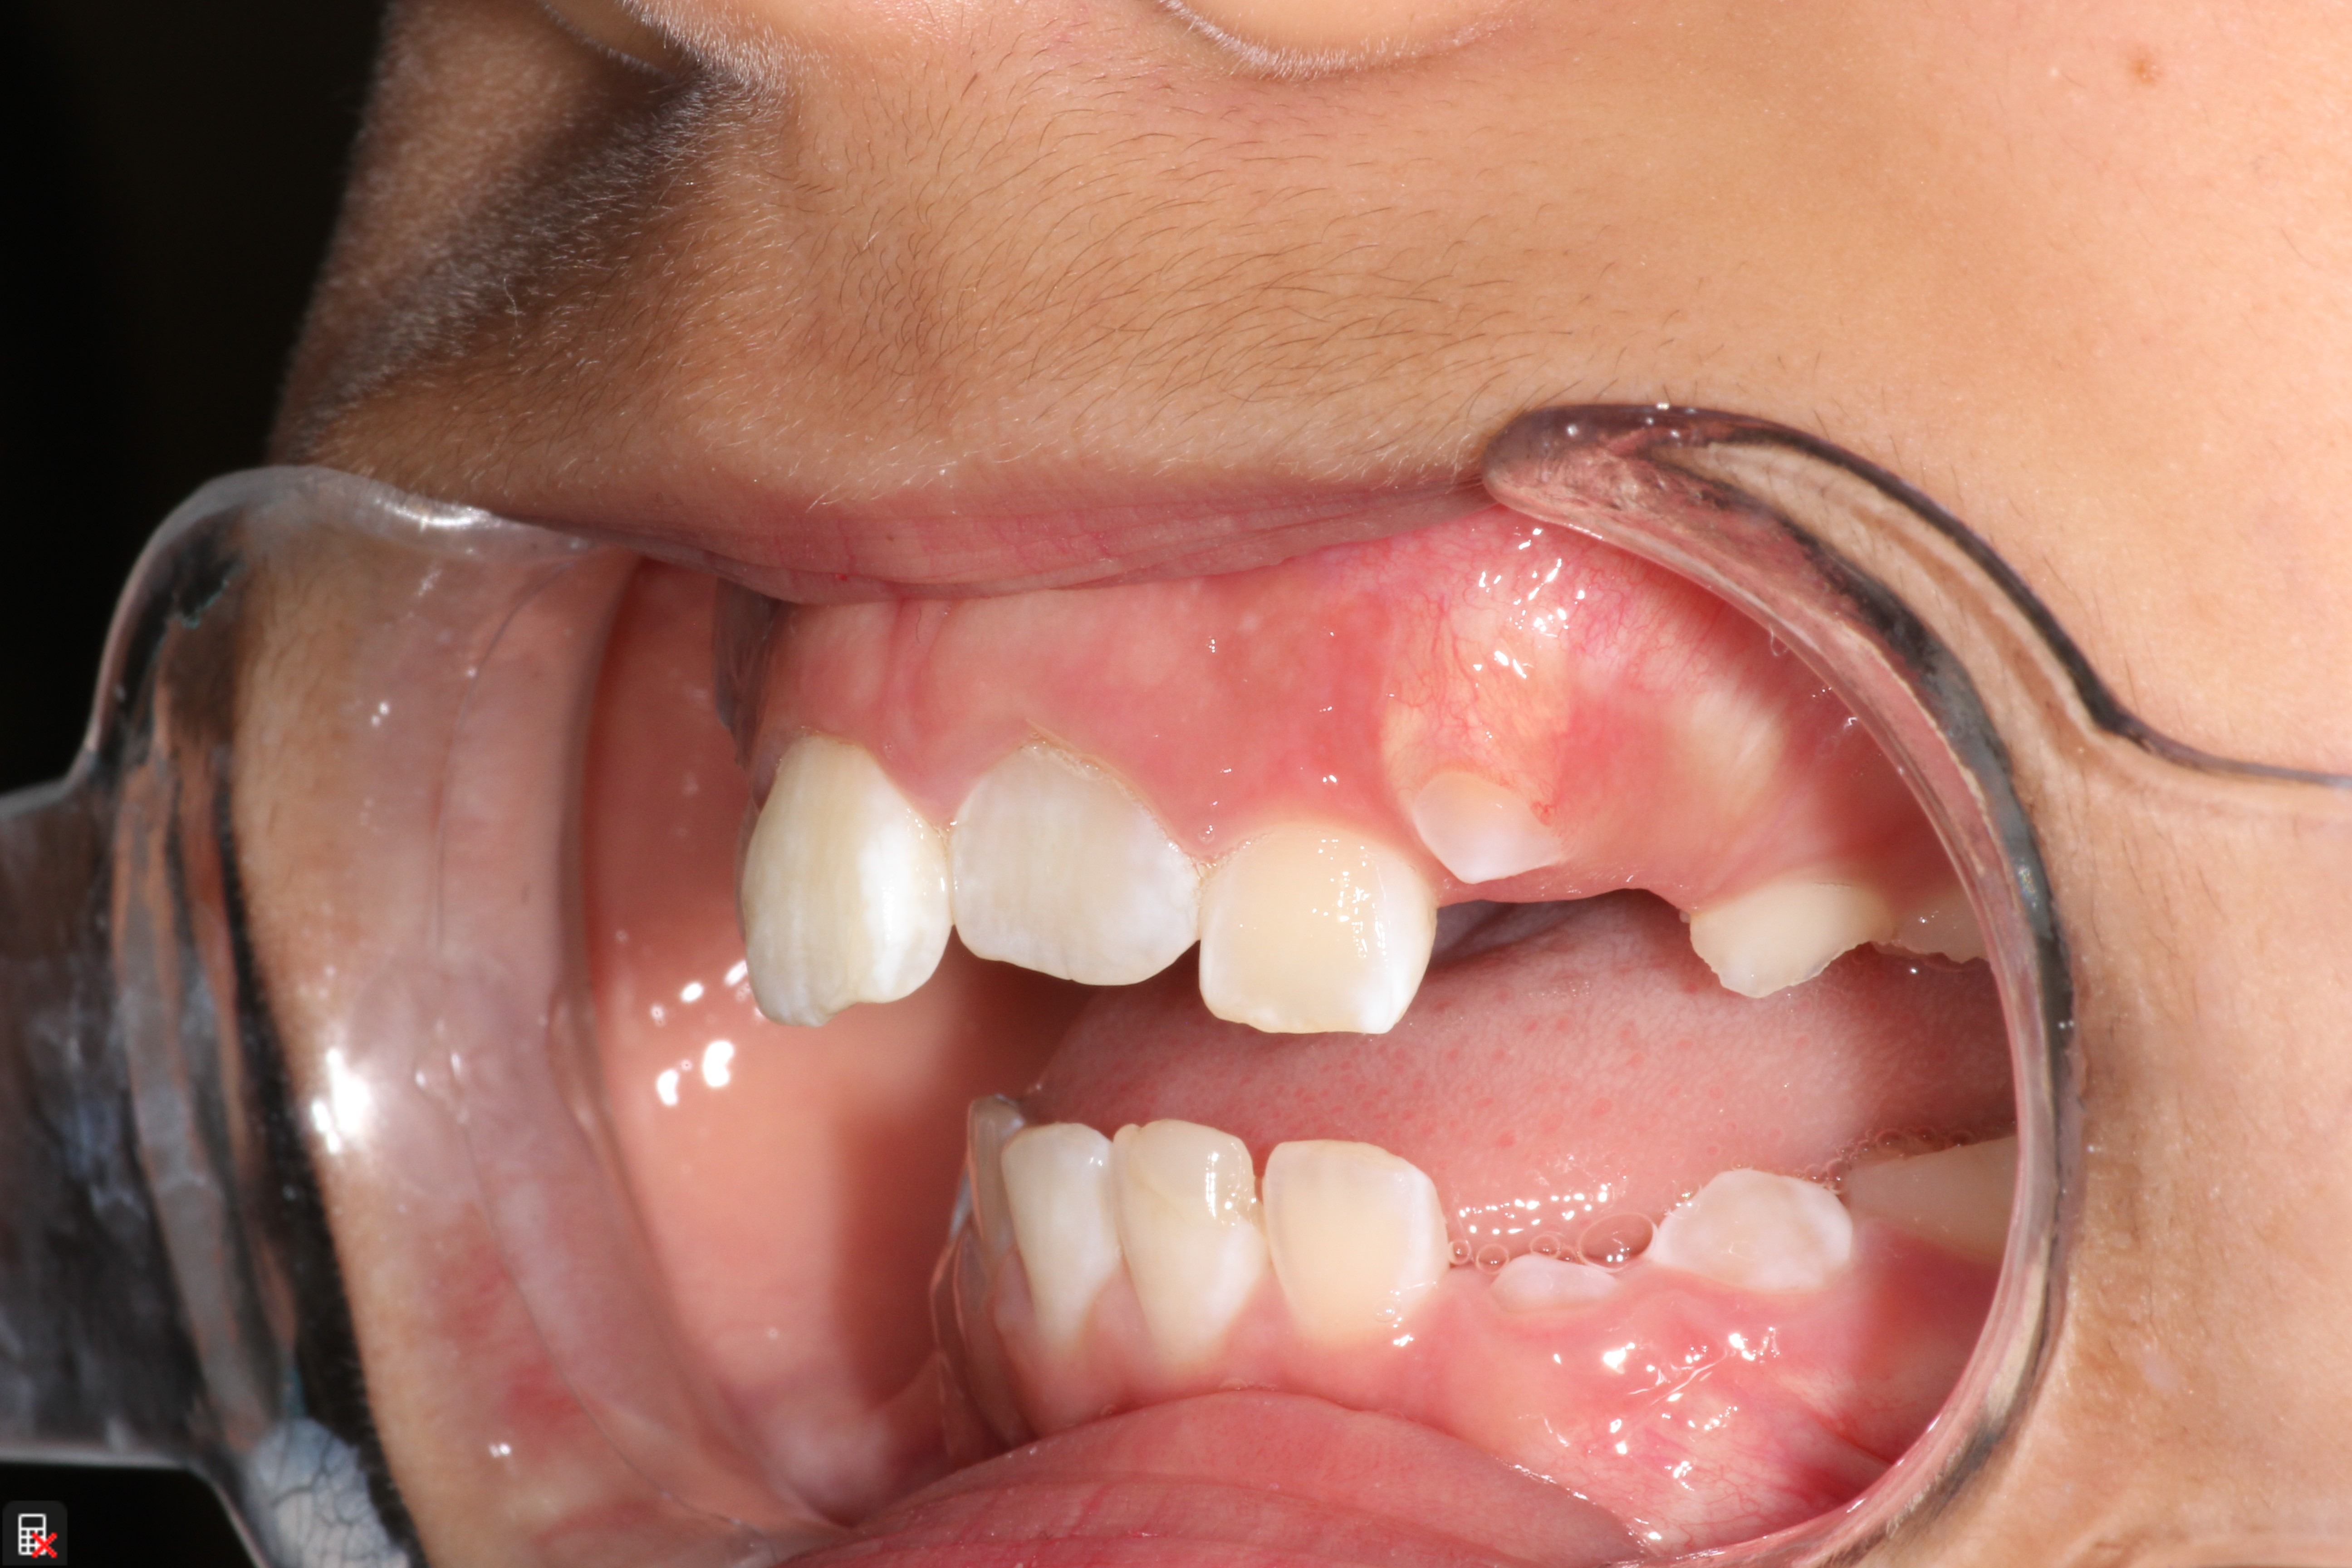

This is a 9yo girl with a high esthetic desire (wants to be a model/actor). She avulsed tooth #9 about 3 years ago, and she has been under treatment with other endodontists. I guess they attempted revascularization with MTA about year ago. #9 is ankylotic with a few mm’s infraposition. It is gray due to the MTA. #8 is slightly yellow/white due to calcification/obliteration but she says she feels cold testing and it is otherwise asymptomatic.

I spoke to her about the following options for #9:

1) Decoronation and a fake tooth for her teenage years

2) No treatment, except internal bleach then bonding/veneer.

3) Autotransplantation of a mandibular premolar

4) Segmental osteotomy/corticotomy later

Are they any other options available? How would you approach this case? Thanks in advance!